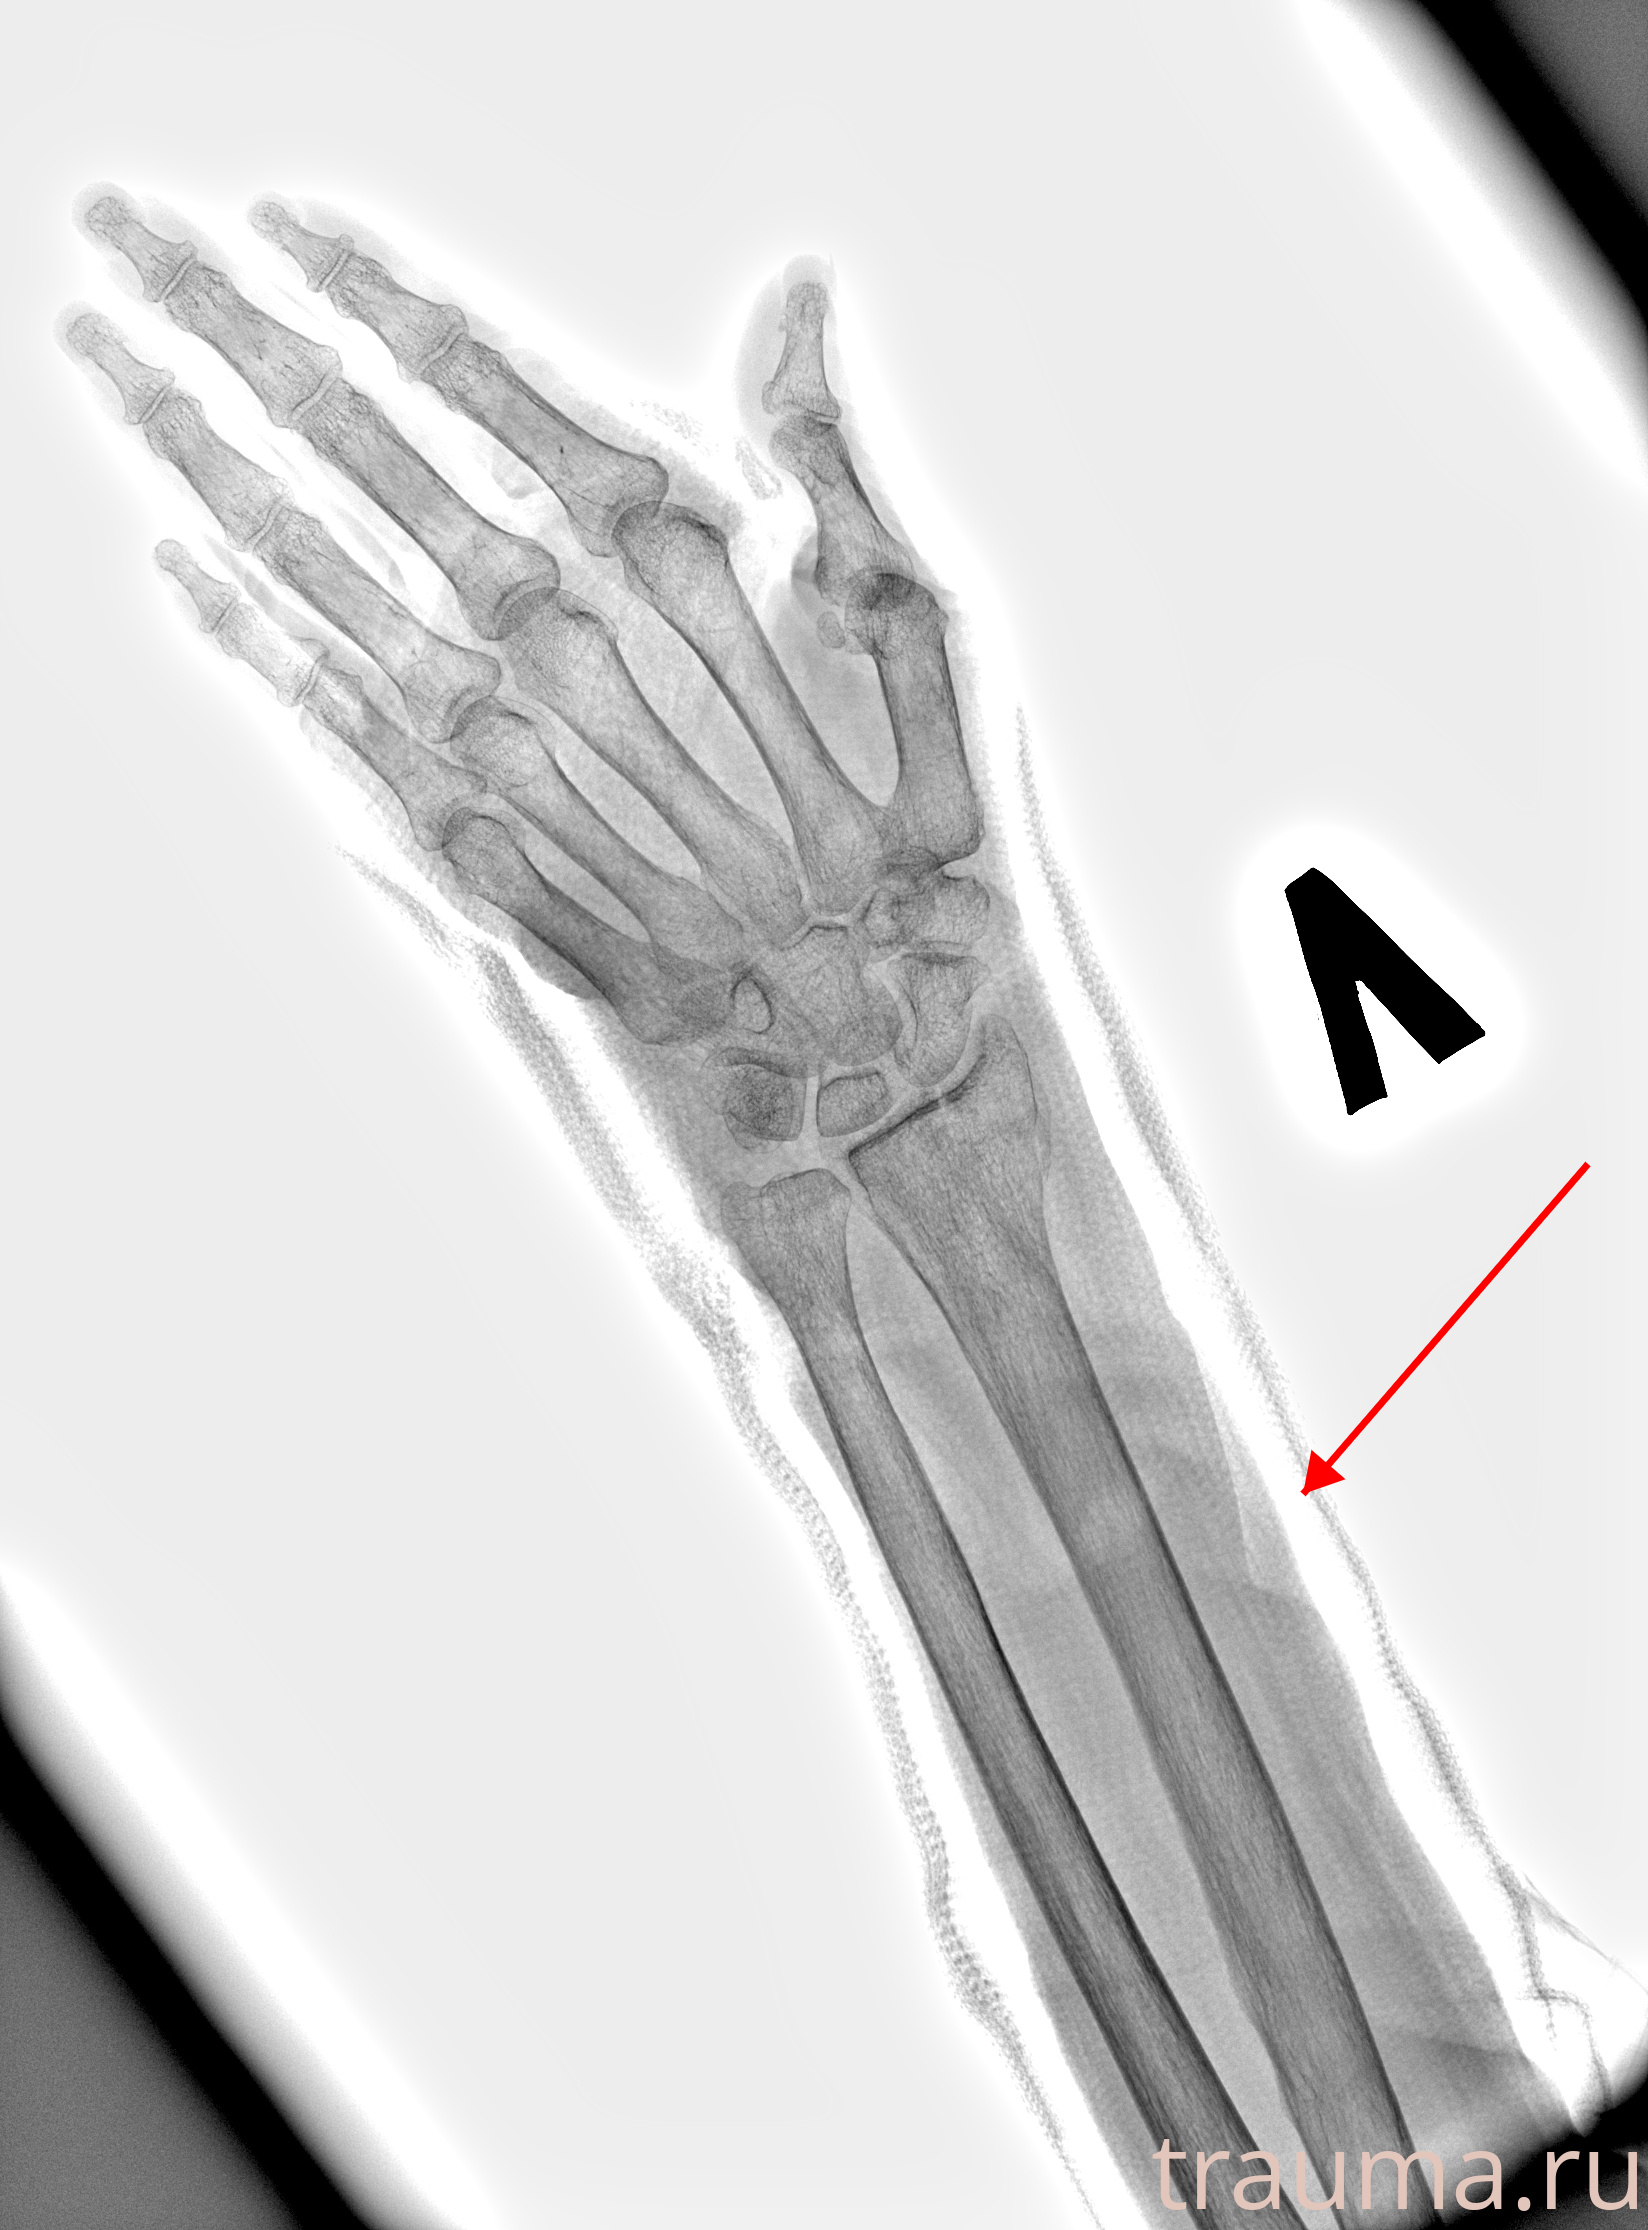

Рентген на дому: по вашему адресу приезжает врач-рентгенолог, травматолог-ортопед с мобильным рентгеновским аппаратом, проводит диагностику травмы или заболевания, делает необходимые рентгенограммы, дает рекомендации по дальнейшему лечению. Получить качественные снимки в домашних условиях возможно благодаря уникальной методике, разработанной МосРентген Центром для института  Склифосовского